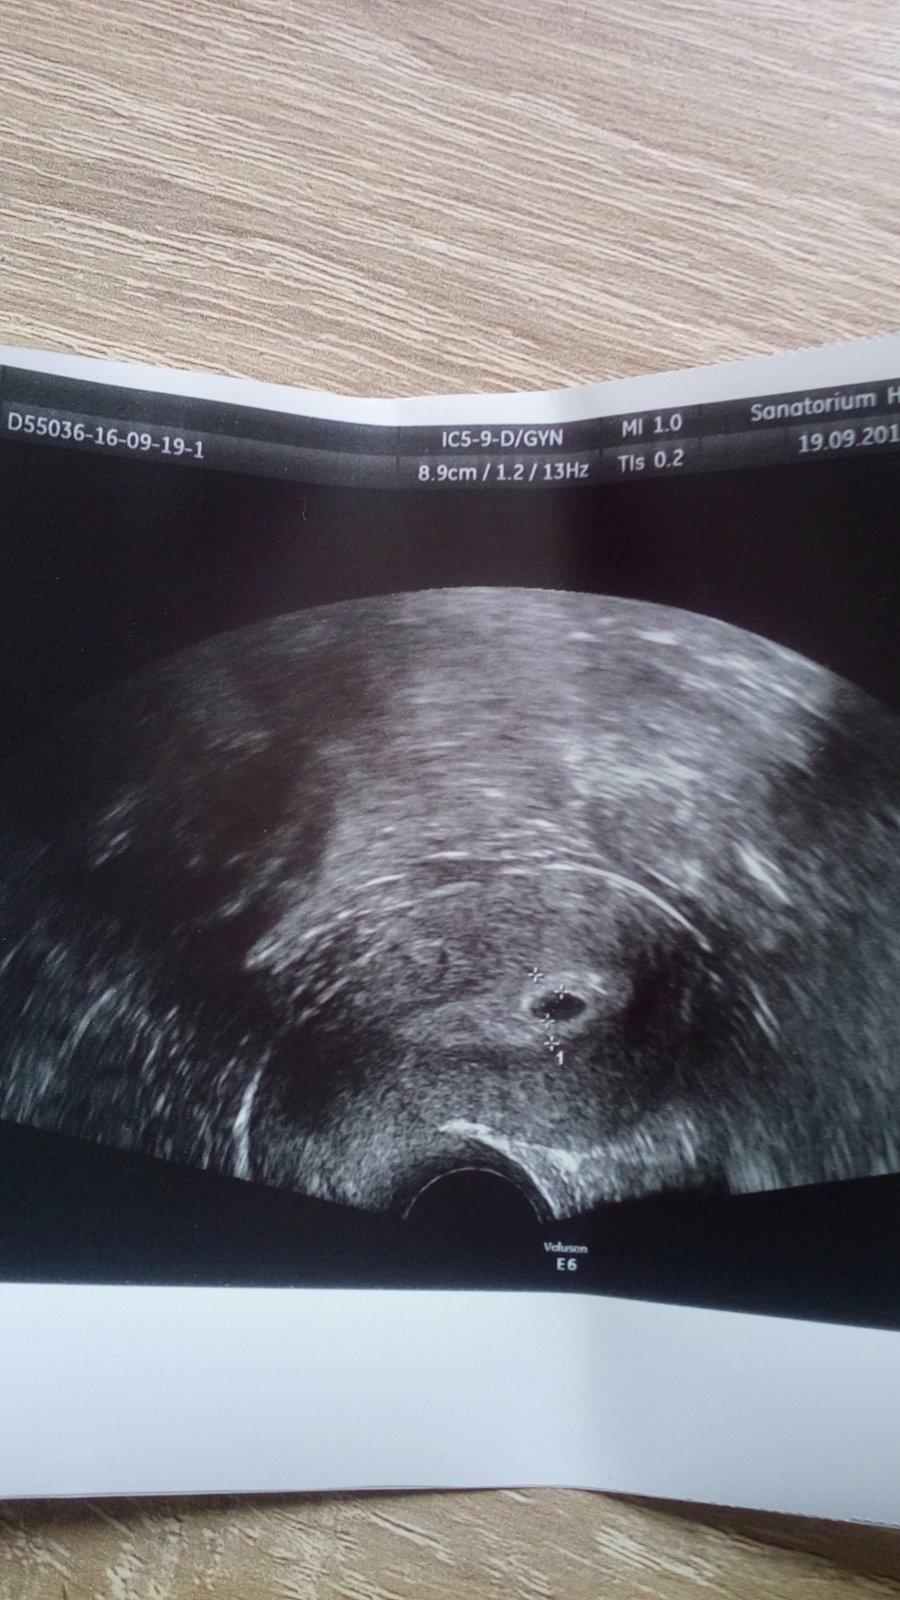

Ahojte baby ,tak som prišla práve z Heliosu.Bublinka má cca 8 mm,srdiečko ešte nie je vidno,na kontrolu idem aaaaaaž 26.9 čiže zas a znova musím čakať...☹